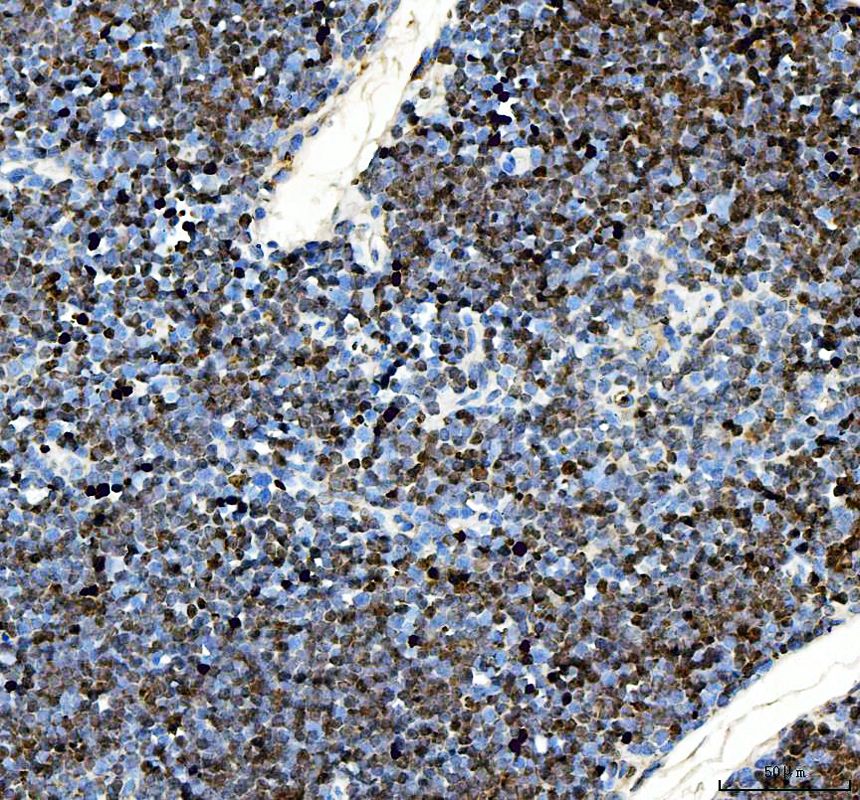

IHC analysis of Ki67/MKI67 using anti-Ki67/MKI67 antibody (PB9026).

Ki67/MKI67 was detected in a paraffin-embedded section of mouse thymus tissue. The tissue section was incubated with rabbit anti-Ki67/MKI67 Antibody (PB9026) at a dilution of 1:200 and developed using HRP Conjugated Rabbit IgG Super Vision Assay Kit (Catalog # SV0002) with DAB (Catalog # AR1027) as the chromogen.